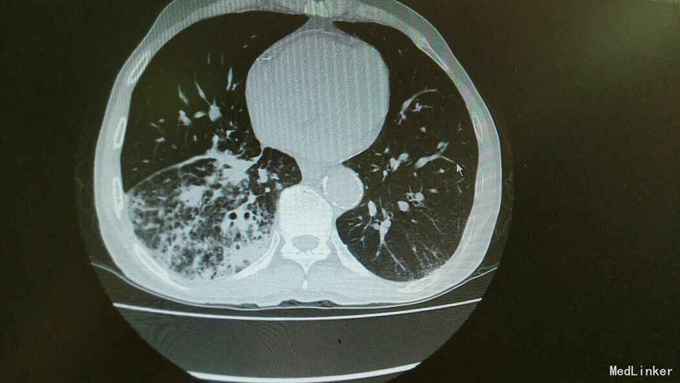

主诉:活动后气促,胸闷1年,消瘦8月余。 病史:患者1年前无明显诱因出现活动后气促,胸闷,主要为胸骨段,爬坡可诱发,伴有咳嗽,白色粘痰。伴有体重下降。

查体:慢性病容,桶状胸,双肺呼吸音粗,右下肺可闻及少量细湿罗音。 辅查:胸部CT:考虑右下肺中央型肺癌并癌性空洞形成,右下肺阻塞性肺炎 ,右下肺动静脉受累,纵隔,双侧肺门多发淋巴结肿大。

诊断:中央型肺癌并阻塞性肺炎。 治疗:入院予以抗感染,止咳化痰等治疗。